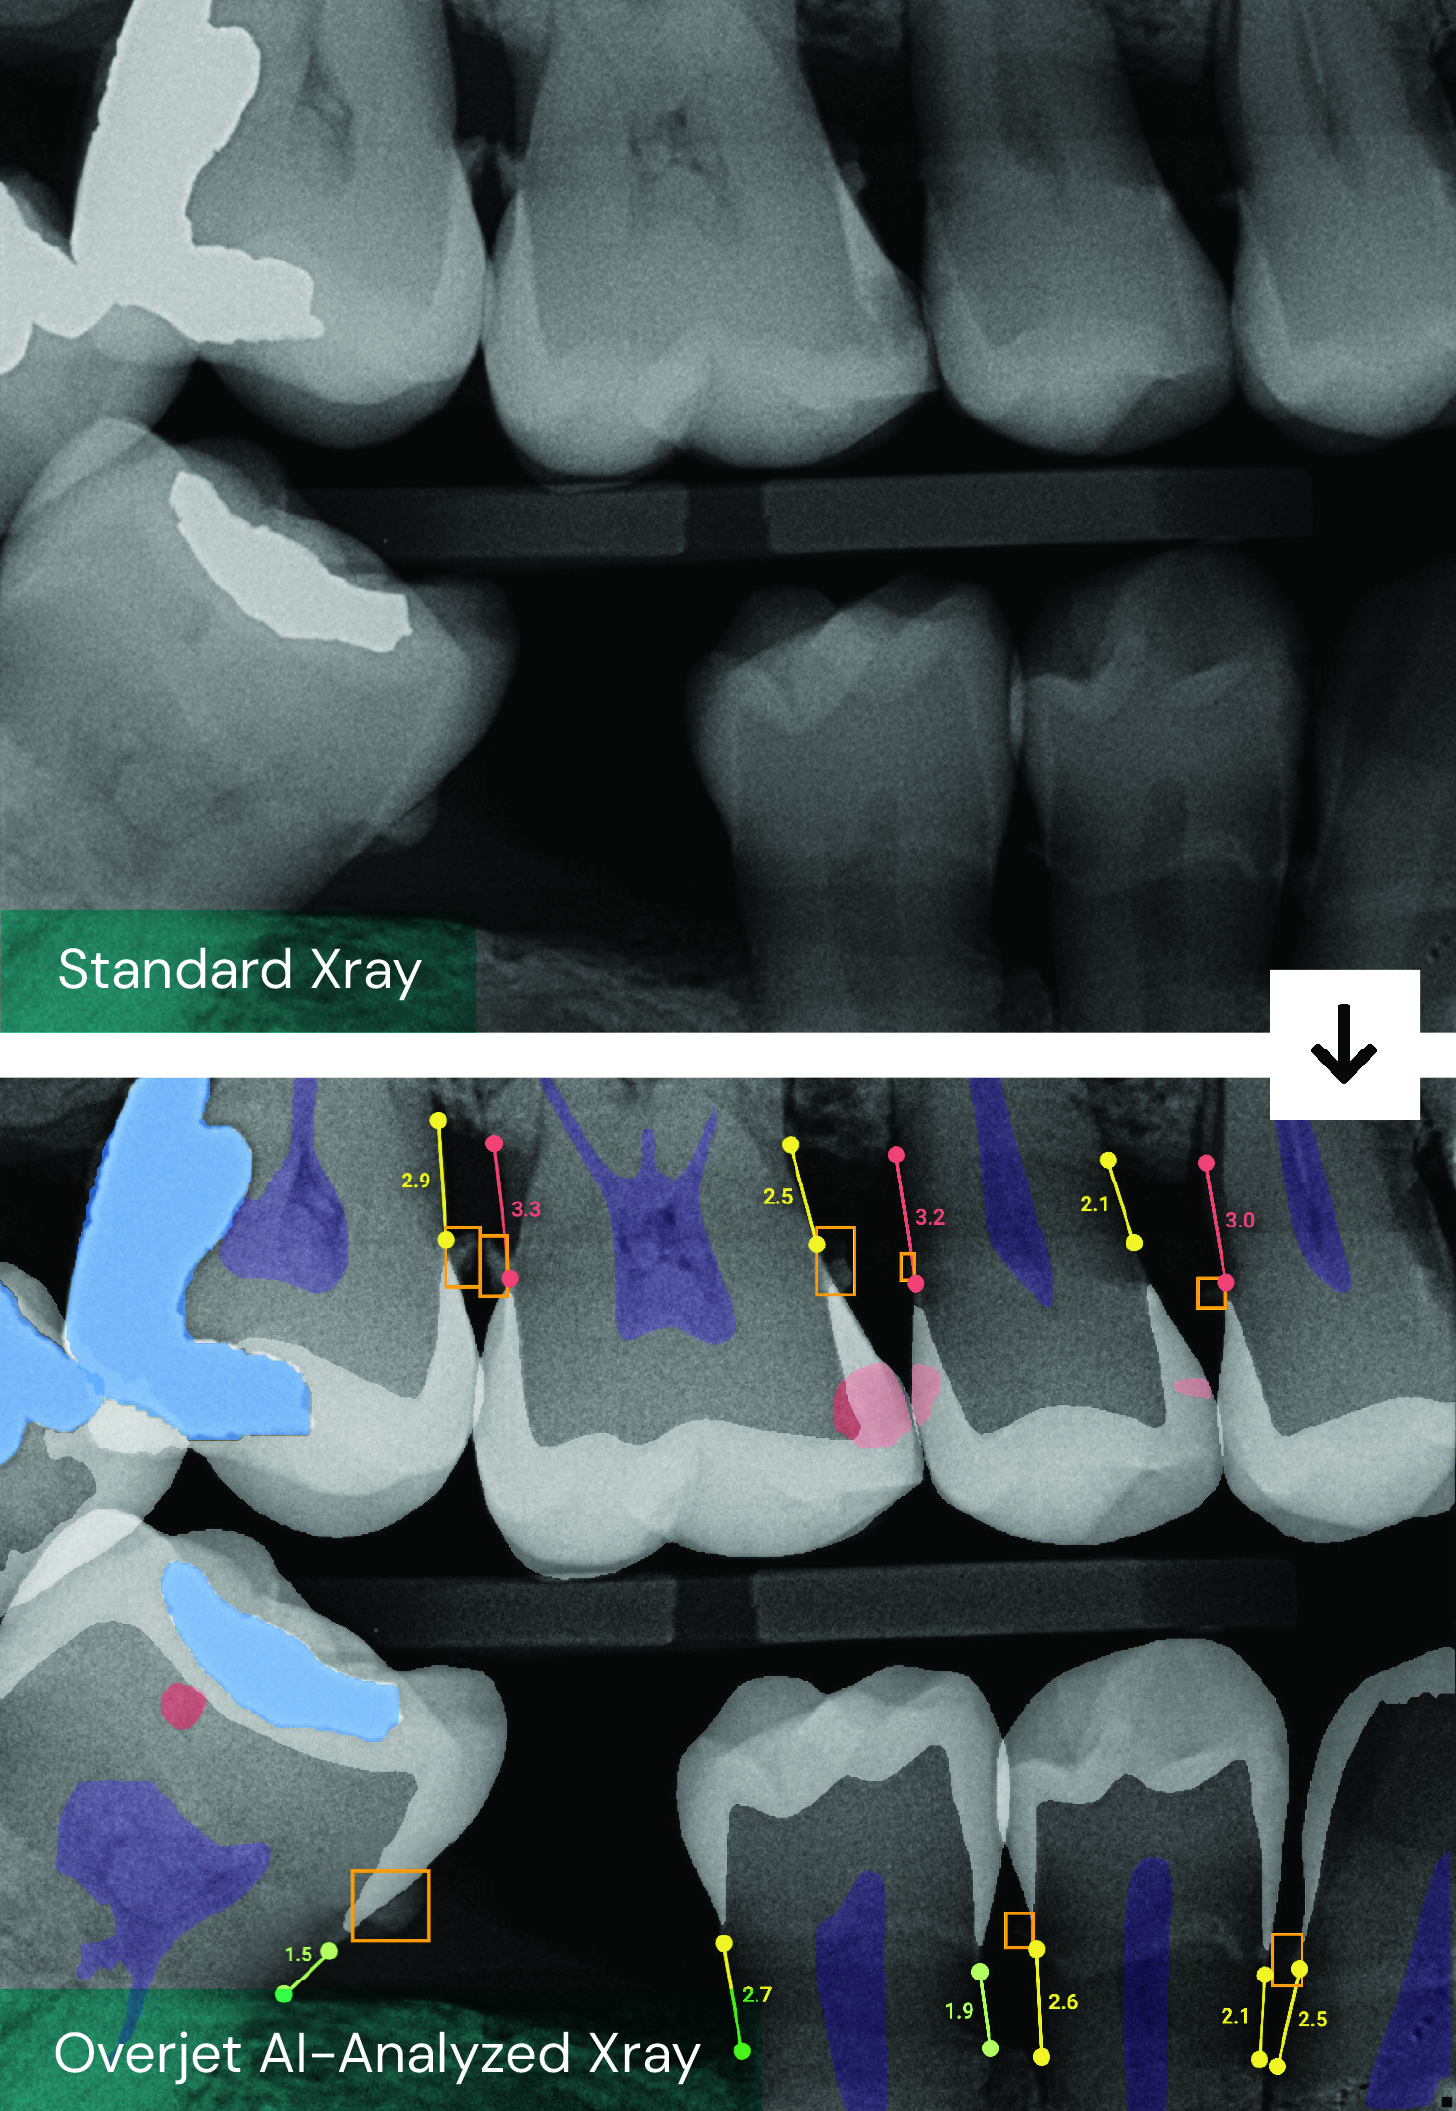

By analyzing dental images and patient data, the platform ensures that diagnoses and treatment plans are consistent, transparent, and aligned with best practices.

From the patient’s perspective, the dental journey—from diagnosis to treatment, claim submission, and payment—can feel complicated and opaque. Instead, Inam argues the journey should be more collaborative at every step. “Our AI-native imaging software helps providers communicate more effectively, so patients truly understand their oral health and the treatments they need,” Inam says.